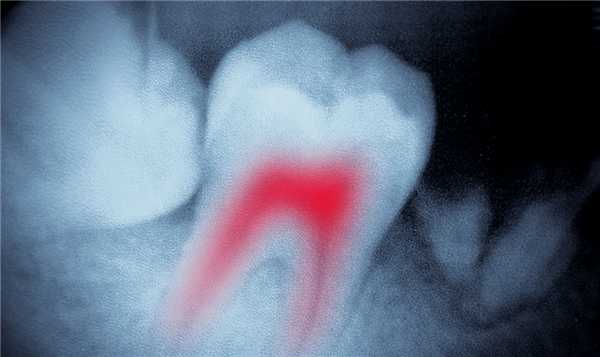

- Дентальная рентгенография. Нередко радикулярная киста выявляется случайно в процессе лечения других зубов. Данное образование на рентгенограмме представляет собой круглую или овальную тень с четкими границами, расположенную у верхушки корня зуба или прилежащую к боковой стенке корня. Костная структура периодонтальной щели разрушена и на снимке не визуализируется. Корни соседних зубов смещены. В ряде случаев идентифицировать кисту не удается даже на рентгеновском снимке, из-за того что корень причинного зуба попадает в зону видимости недостаточно полно.

КТ челюстно-лицевой области. Радикулярная киста (красная стрелка) вблизи корня левого клыка верхней челюсти, состояние после эндодонтического лечения (синяя стрелка - филлер в корневом канале), избыток филлера за пределами верхушки зуба (зеленая стрелка).